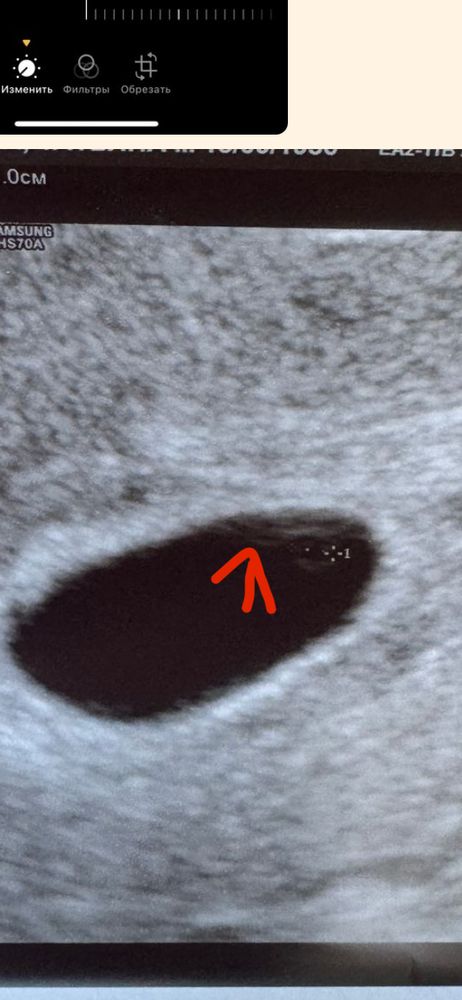

квитка, добрый день, может и у меня на снимке вы что нибудь разглядите ?)) 26дпп Изображение Изображение

Вероника, я вижу желточный мешочек и эмбрион, а врач узи что ваш увидел?)

квитка, вот эта линия похожа на эмбриошу Изображение

квитка, пока что только ЖМ 1,7мм и все, сказала замершая 😭 тк нет эмбриона. Плоднле яйцо 11,4мм. В четверг пойду к своей ре

Вероника, на таком сроке не ставят замершую , ставят в 8 недель если ничего нет